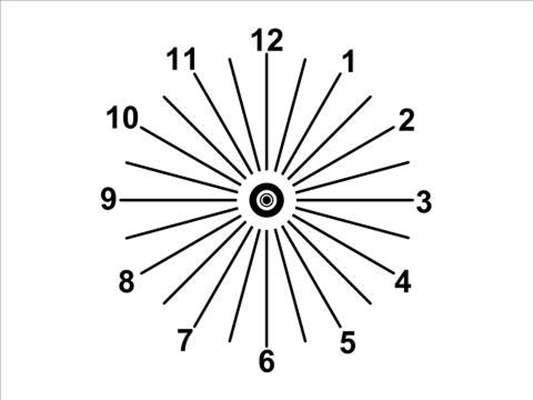

散光圖片

A:判斷自己有沒有散光,最簡單的方法是使用散光表來測試。散光表是一種簡單、方便的方法,但是它的準確度不是特別精確。在配鏡的情況下一般再用裂隙法,或者是交叉圓柱鏡法來精調散光的度數。散光表在網上可以看到,它類似於鐘錶的盤面,有12個數字。各個鏡線……